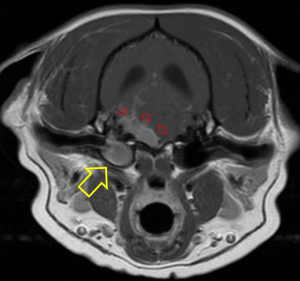

Quando escolher Ressonância Magnética (RM)?

A RM é superior na avaliação de tecidos moles, como cérebro, medula espinhal, nervos, ligamentos e estruturas internas delicadas.

Ela usa campos magnéticos e ondas de rádio — sem radiação — oferecendo imagens detalhadas e seguras.

É o exame mais indicado para:

• Lesões cerebrais

• Tumores

• Encefalites

• Doenças degenerativas

• Extrusões discais

• Lesões intramedulares

A RM utiliza campos magnéticos poderosos e pulsos de radiofrequência para produzir imagens detalhadas dos órgãos, tecidos moles, ossos e outras estruturas internas do corpo.

Dito isso, nos casos em que há suspeita de lesão cerebral, a RM é mais sensível e específica na maioria dos pacientes para diagnosticar tumores cerebrais primários ou metastáticos, encefalite, lesões vasculares e doenças degenerativas.

Para lesões na coluna, a RM é melhor para extrusões discais, tumores de tecidos moles (ex.: meningioma) e lesões intraparenquimatosas (como FCE, meningomielite, siringomielia).